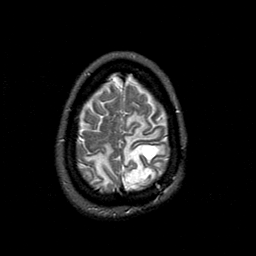

MR Study #1 -- Slice #44